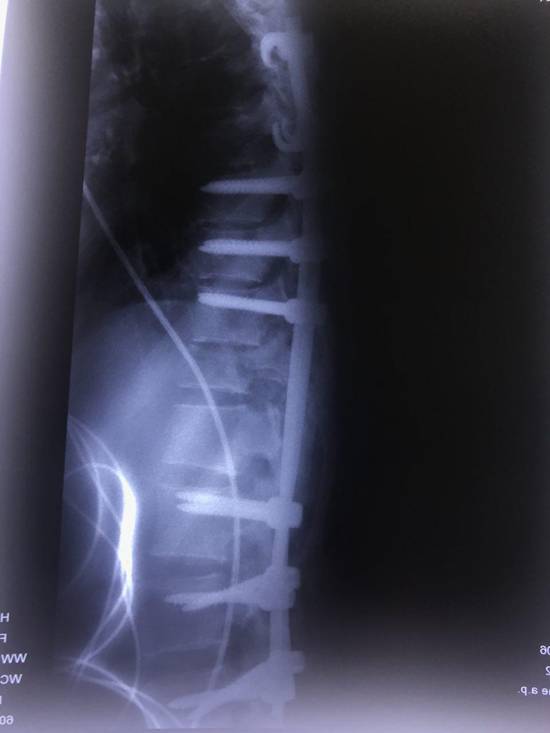

بيمار آقاى 28 ساله در تاريخ 20 آبان 96 در حين خدمت به زائرين محترم امام حسين در كربلاي معلي از ارتفاع نسبتاً زياد روي داربستهاي آهنين سقوط كرده و دچار صدمات شديد مغز و ستون فقرات شد كه عمده ضايعات آن شكستگي وسيع جمجه، كنتوزيون مغزي، كما، شكستگي و در رفتگي مهره 12 پشتي و اول كمري (L1/T12) بود. به علت گسيختگي ستون فقرات بيمار قابل انتقال به ايران نبوده و بلافاصله به بخش ICU بيمارستان امام زين العابدين در كربلا منتقل گرديد. مسئول مربوطه طي تماس با بيمارستان بهمن درخواست اعزام تيم پزشكي به كربلا را نمودند.

تيم پزشكي جناب آقاي دكتر سيد مصطفي سادات،جراح ستون فقرات، به همراه يكي از همكاران زبده خود جناب آقاي دكتر احمدرضا ريحاني و دو تكنسين ورزيده اطاق عمل در كمتر از 24 ساعت با همراه داشتن ست هاي جراحي كامل جهت تثبيت بي ثباتي ستون فقرات و بررسي وضع نخاعي بيمار به كربلا اعزام شدند. بيمار در روز پنجشنبه 25 آبان ماه در اتاق عمل بيمارستان امام زين العابدين كربلا جراحي گرديد كه حدود 4 ساعت به طول انجاميد. در حال حاضر پس از گذشت حدود يك هفته از جراحي وضع هوشياري بيمار بنا به گفته تيم معالج حاضر در كربلا رو به بهبودي مي باشد.